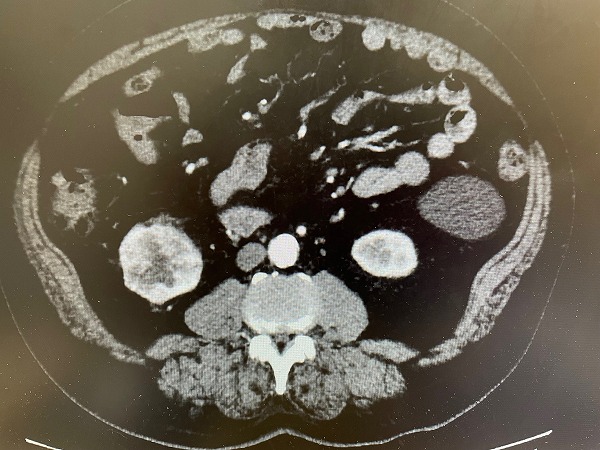

この間、埼玉病院での検査は繰り返された。この映像は1度目の造影剤を入れたCT検査の僕の腎臓の画像。上の画像の左部分の腎臓の下に丸く付いているのが癌の腫瘍。この時点で直径7センチ大だった。下の画像は輪切りにして見ているもの。やはり左部分の丸いものが腎臓がんである。僕が「腎臓よりも大きく見えますね」と言うとまだ40代と思われる執刀を担当する医師は「そうですね、でもまだ転移は見られませんので早く切りましょう」と言って笑った。この写真はその医師が撮影してくれたもの。僕が写真家であり記録として残したいという希望に沿ってくれたのである。

左がわの丸いのが癌の病巣。

左側の腎臓の下にぶら下がる丸いものが癌の腫瘍。